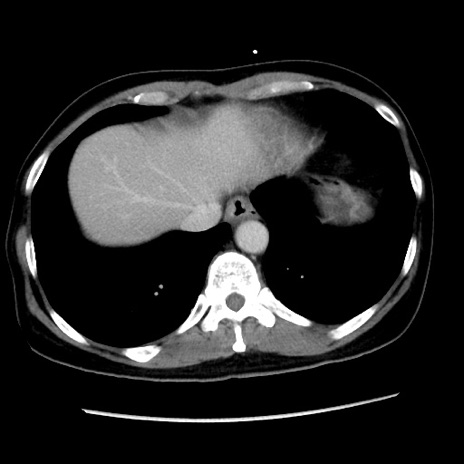

冠状断像

【症例】 50歳代女性

【主訴】 腹痛

【現病歴】前日生レバーを食べた。今朝に排便あり。 昼前に突然発症の腹痛を生じ、当院救急外来を受診した。

【身体所見】 意識清明、腹部:平坦、軟、下腹部やや左を中心に圧痛・反跳痛あり、筋性防御あり